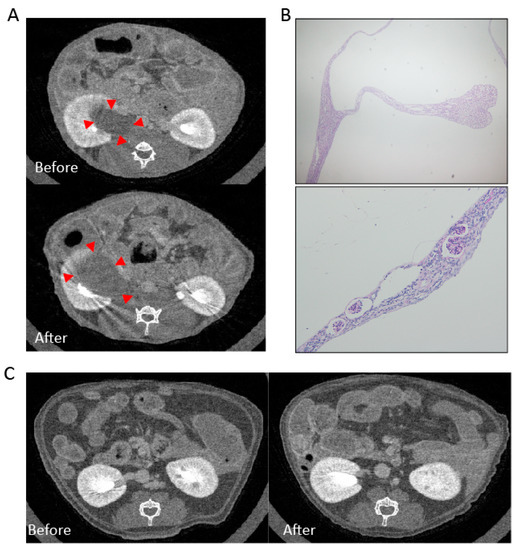

2.1. Case Report

2.2. Experimental Animal Model

2.2.1. Mesangial Expansion in Crizotinib-Treated Mouse

2.2.2. Crizotinib Caused Renal Histopathological Changes